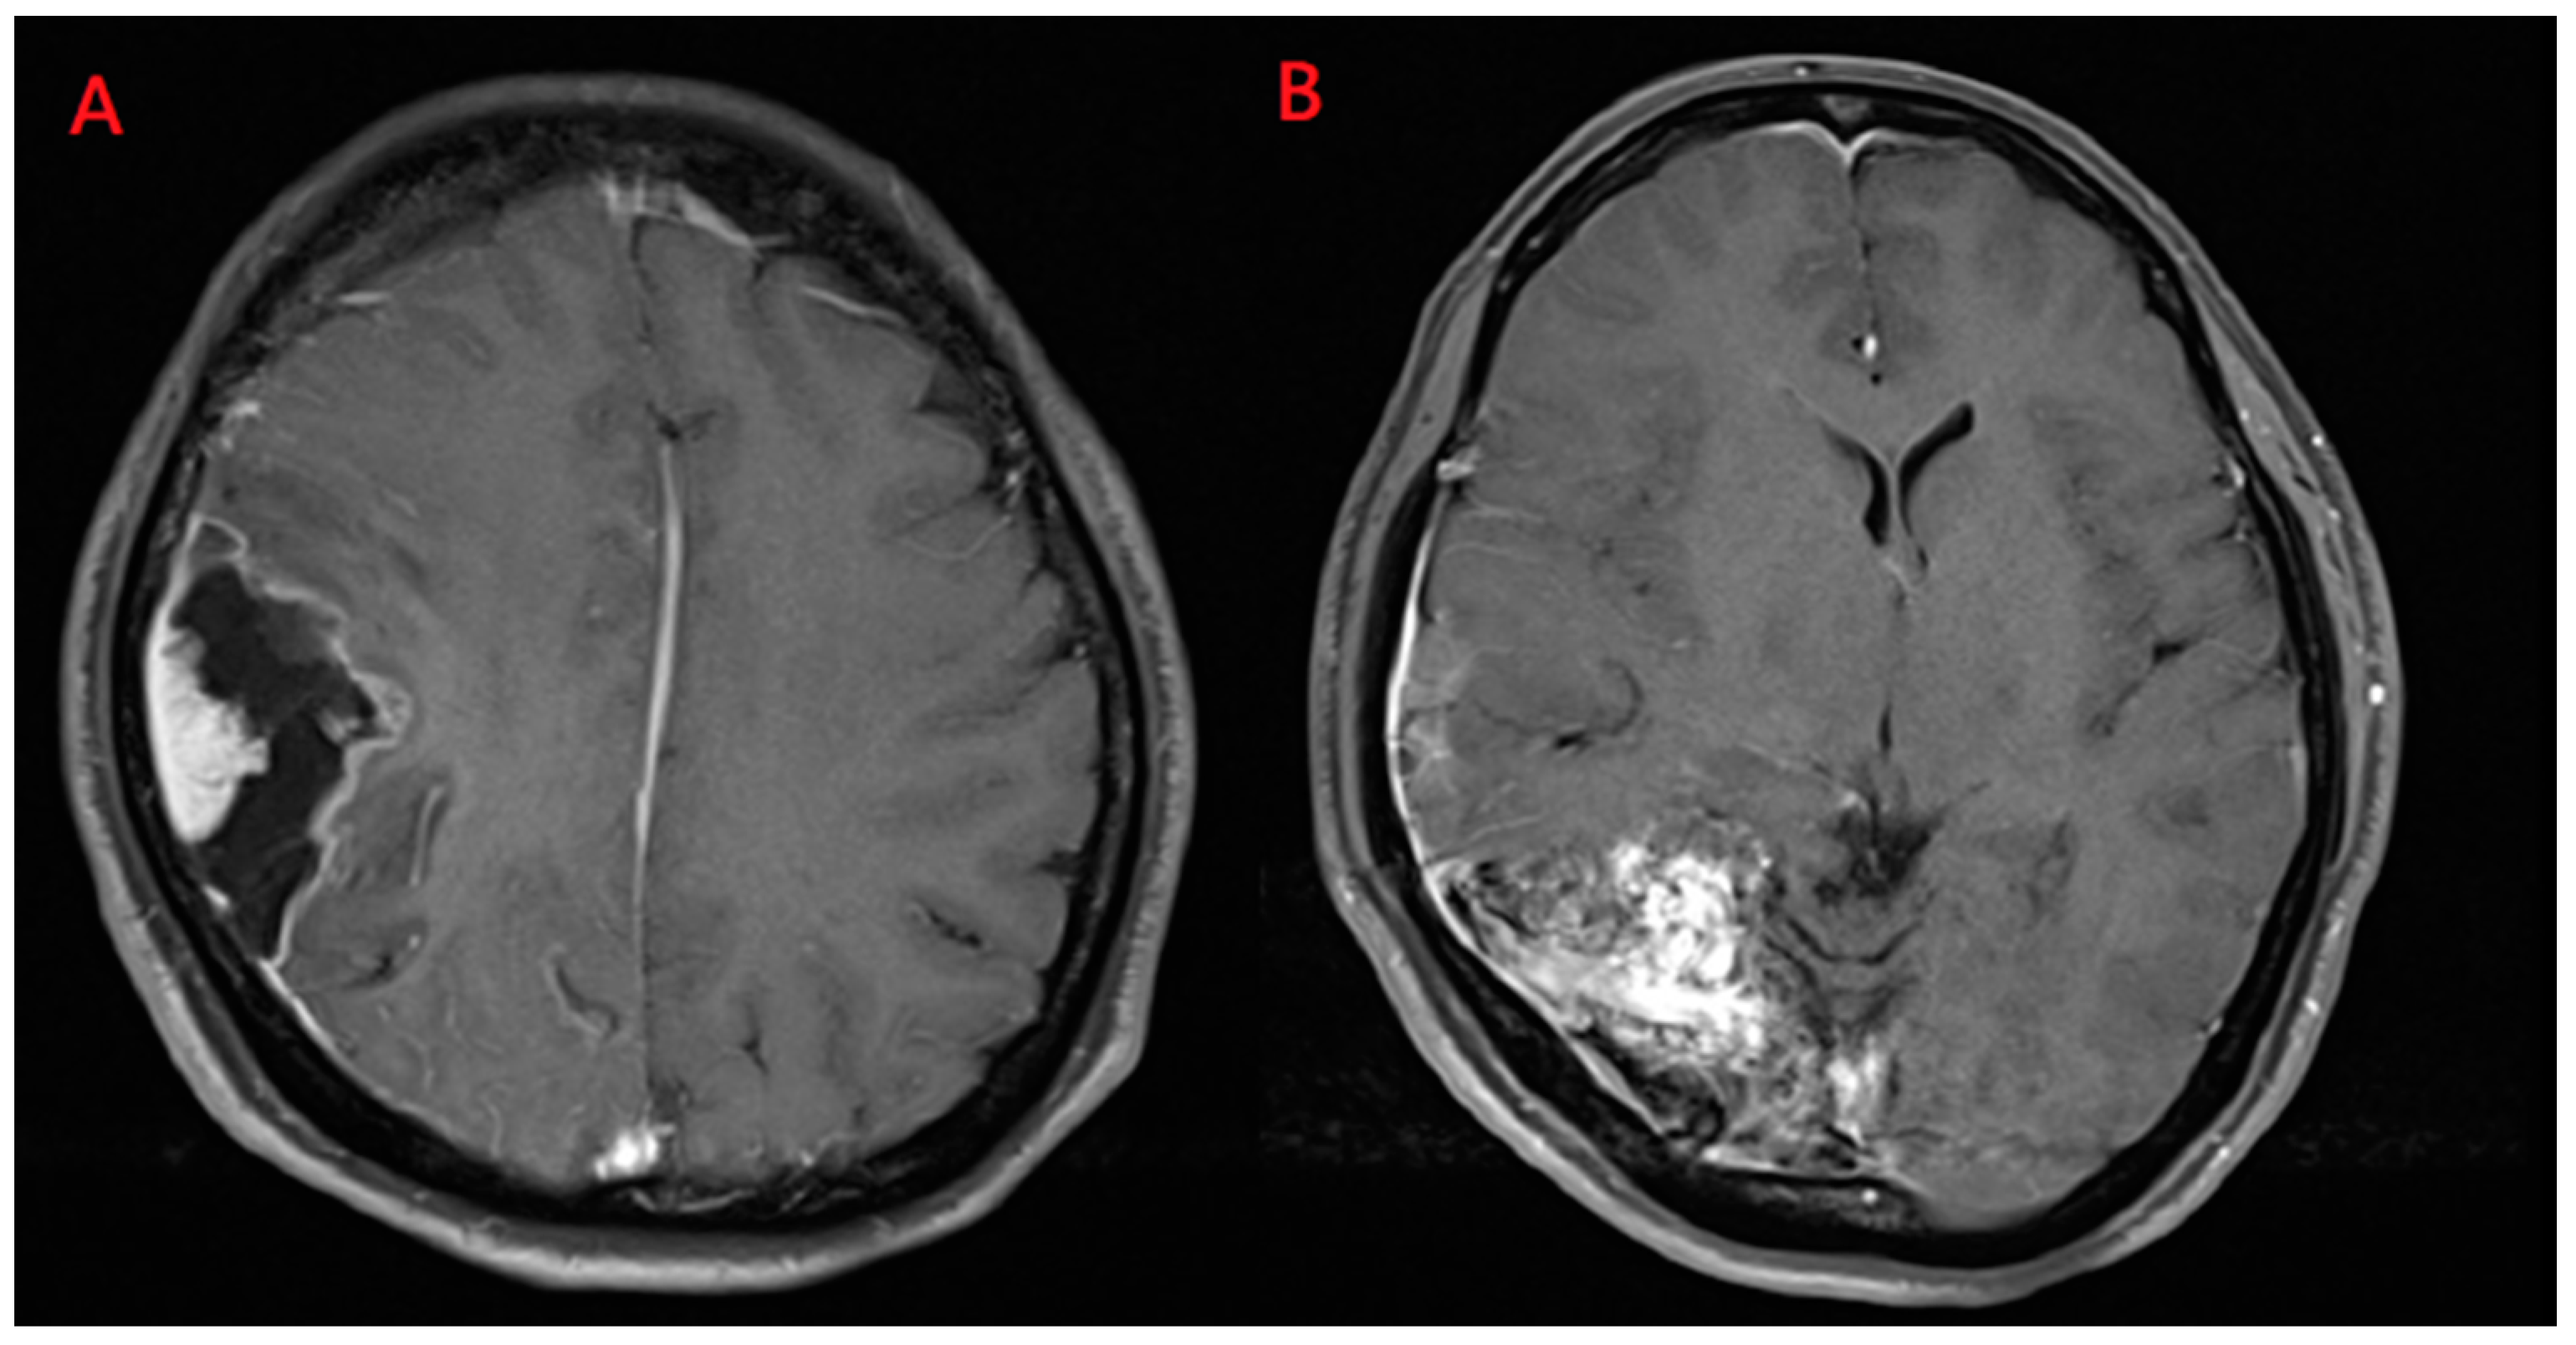

Magnetic resonance imaging (MRI) demonstrated a well enhanced mass, 1.1 cm × 2.3 cm in size, with a peri-focal edema in the right temporal lobe Figure 2A. In addition, surrounding and tangled dilated vessels in the right temporo-occipital area were noted on T1-weighted with gadolinium Figure 2B. Computed tomographic angiography (CTA) also confirmed these lesions Figure 3. Upon additional CTA study, the presence of arteriovenous malformation (AVM) nidus at the right temporal-parietal occipital region with arterial feeding from the right middle cerebral artery (MCA) and posterior cerebral artery (PCA), which then drained to the right transverse-sigmoid sinus via an engorged drainage vein, was noted.

Figure 2.

Magnetic resonance imaging scans. (A) Heterogeneously enhanced mass, 1.1 cm × 2.3 cm in size, with perifocal edema in the right temporal lobe was noted; (B) Surrounding and tangled dilated vessels in the right temporo-occipital area were observed on T1-weighted images with gadolinium.